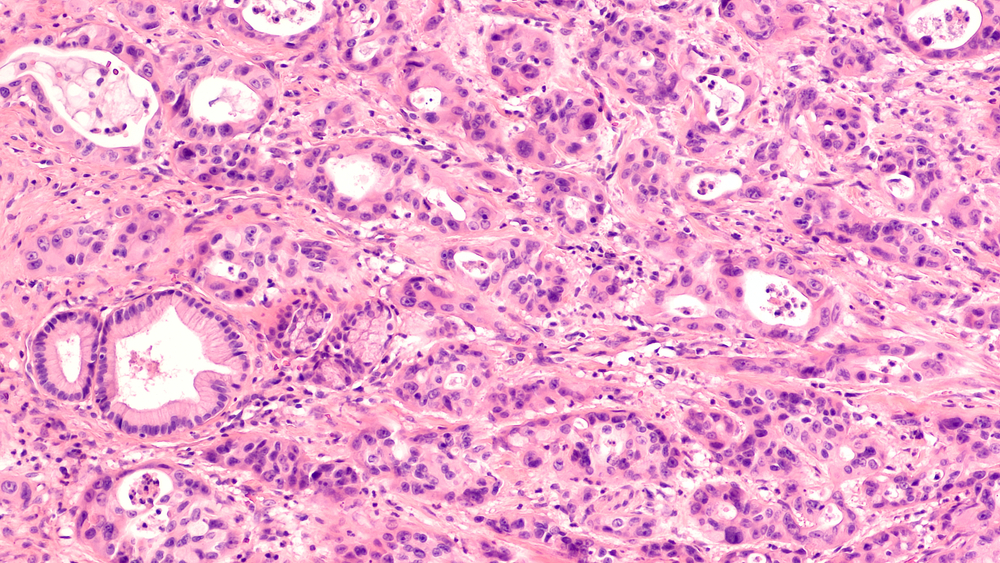

Pancreatic cancer is notoriously difficult to treat because of the dense scar tissue surrounding tumours – the tissue acts like a fortress that blocks chemotherapy delivery.

“This scar tissue is produced by critical ‘helper cells’ – also called cancer-associated fibroblasts – which cancer cells recruit to support their growth and spread. Yet, these helper cells have been ignored in current treatment strategies,” A/Prof. Phillips says.

In today’s paper, the team demonstrates their novel way to metabolically rewire helper cells by targeting one particular protein called SLC7A11, which in turn shuts off the cells’ tumour-promoting activity and reduces the scar tissue they produce.

“We found that switching off SLC7A11 in mice with pancreatic tumours directly killed pancreatic cancer cells, reduced the spread of tumour cells throughout their body and decreased the scar tissue fortress,” says Dr George Sharbeen, a postdoc researcher in A/Prof. Phillips’ lab who led the experimental work.